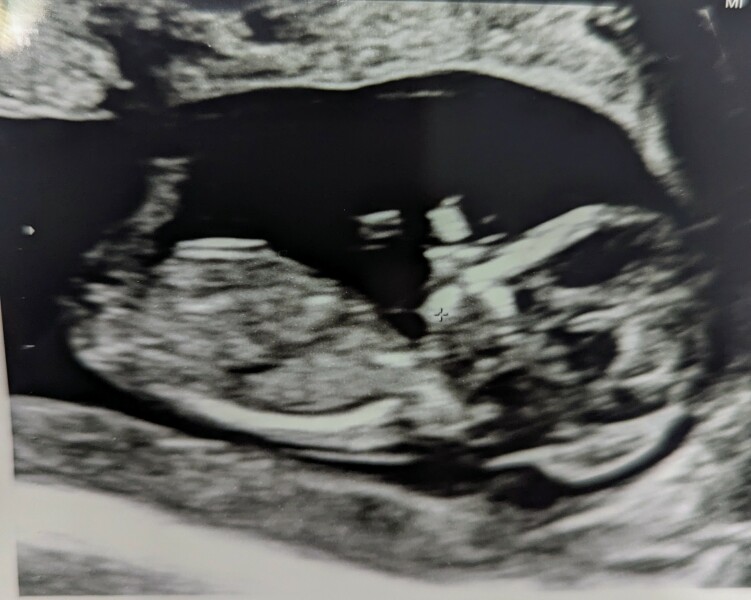

@CatiaR Aw congratulations, what a lovely little baby! Are you interested in gender nub theory? I think I might be able to take a guess 👀

@etaketak1991 thanks! well we are not planning to find out but everyone already been taking guesses even before they have seen the scan picture so you're welcome to take a guess as well if you want :) I have seen those around but honestly have no clue what I am looking at and other scan pictures we have look a bit different than that one so couldn't tell either way

@CatiaR It's all just guesswork isn't it, even sonographers get it wrong sometimes! I think based on that photo you might have a girl there 🩷 Our scan was much blurrier 😂

ah I see it’s a bit more blurry yeah. It took our sonographer a long while till they could take a nice picture or even do the last measurements since baby wouldn’t stop moving around 😂